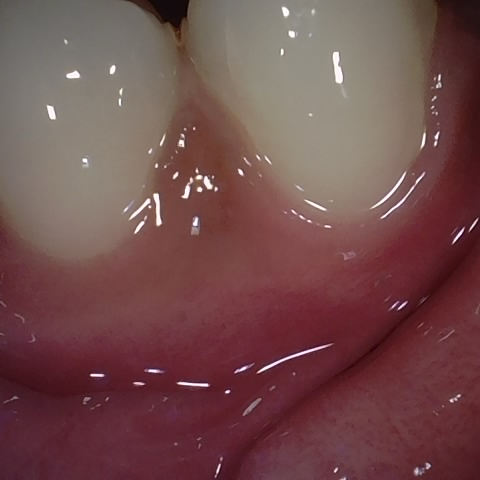

Image 73 / 400

NHD25466

Annotated as "Bad"

Original Image Rendering Image